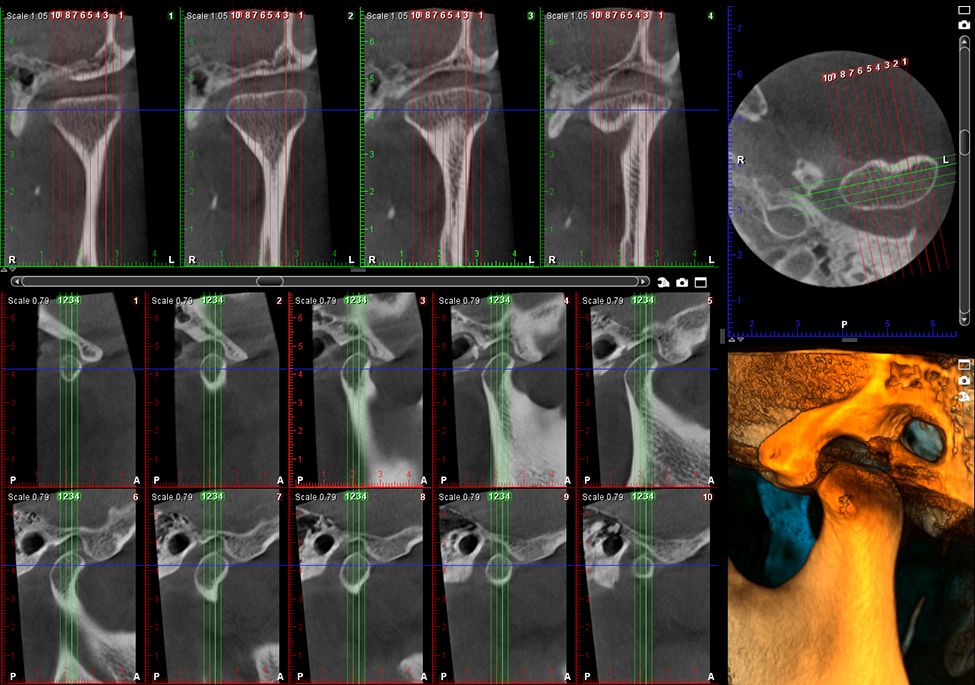

Obrazy Kliniczne Planmeca ProMax 3D s

Szczegółowe obrazowanie 3D

Specjalny tryb obrazowania endodontycznego pozwala na tworzenie szczegółowych, trójwymiarowych zdjęć. Woksele o rozdzielczości 75 μm zapewniają wyjątkową jakość obrazu, uwzględniając nawet najdrobniejsze detale.